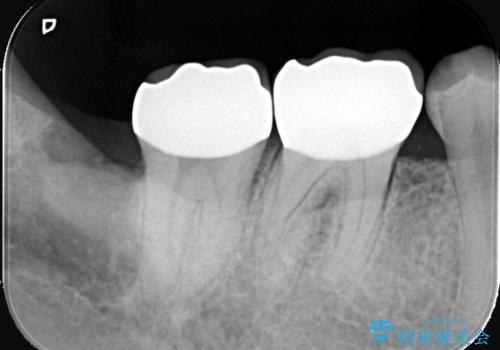

歯の根元の虫歯も精密治療で解決

- 右下6番と7番の奥歯に、歯の根元部分の虫歯(根面カリエス)を認め来院されました。通常の虫歯よりも進行しやすい根面カリエスは、再発リスクを抑えた治療が重要です。患者様のご希望と口腔内の状態を考慮し、虫歯を徹底的に除去し、精密で耐久性の高いセラミッククラウンで修復する治療計画を立案しました。これにより、長期的な再発防止と咬み合わせの機能回復を目指します。

治療ではまず、感染した歯質をマイクロスコープで確認しながら慎重に除去。その後、セラミッククラウンを装着するための歯の形成を行いました。型取りから患者様の歯の形や色に合わせたオーダーメイドのセラミッククラウンを作製。セラミックは、プラークが付着しにくく、再治療のリスクを低減する特性があります。最終的に、精度の高いクラウンを装着し、咬み合わせを細かく調整しました。これにより、根面カリエスが再発しにくい環境を整え、快適に食事ができる奥歯を取り戻していただけました。